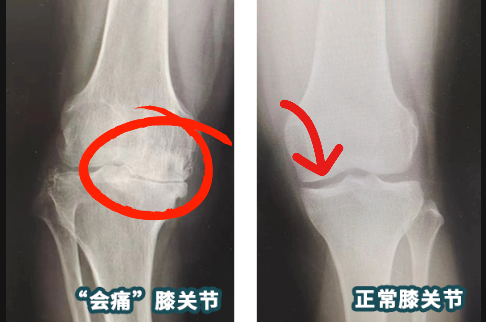

在betway在线登陆关节外科,副主任医师郝亮为王钢进行了仔细检查,X线显示其膝关节退变,关节间隙明显变窄,并出现跛行、膝关节内翻、肿胀等明显症状,综合判断其为“右膝关节骨关节病”。

简单来说,关节间隙的消失,导致骨与骨直接摩擦,因此出现疼痛等症状。